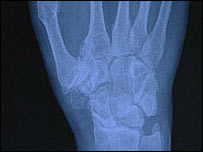

手部的X光照片

伦凯伊手部的X光照片